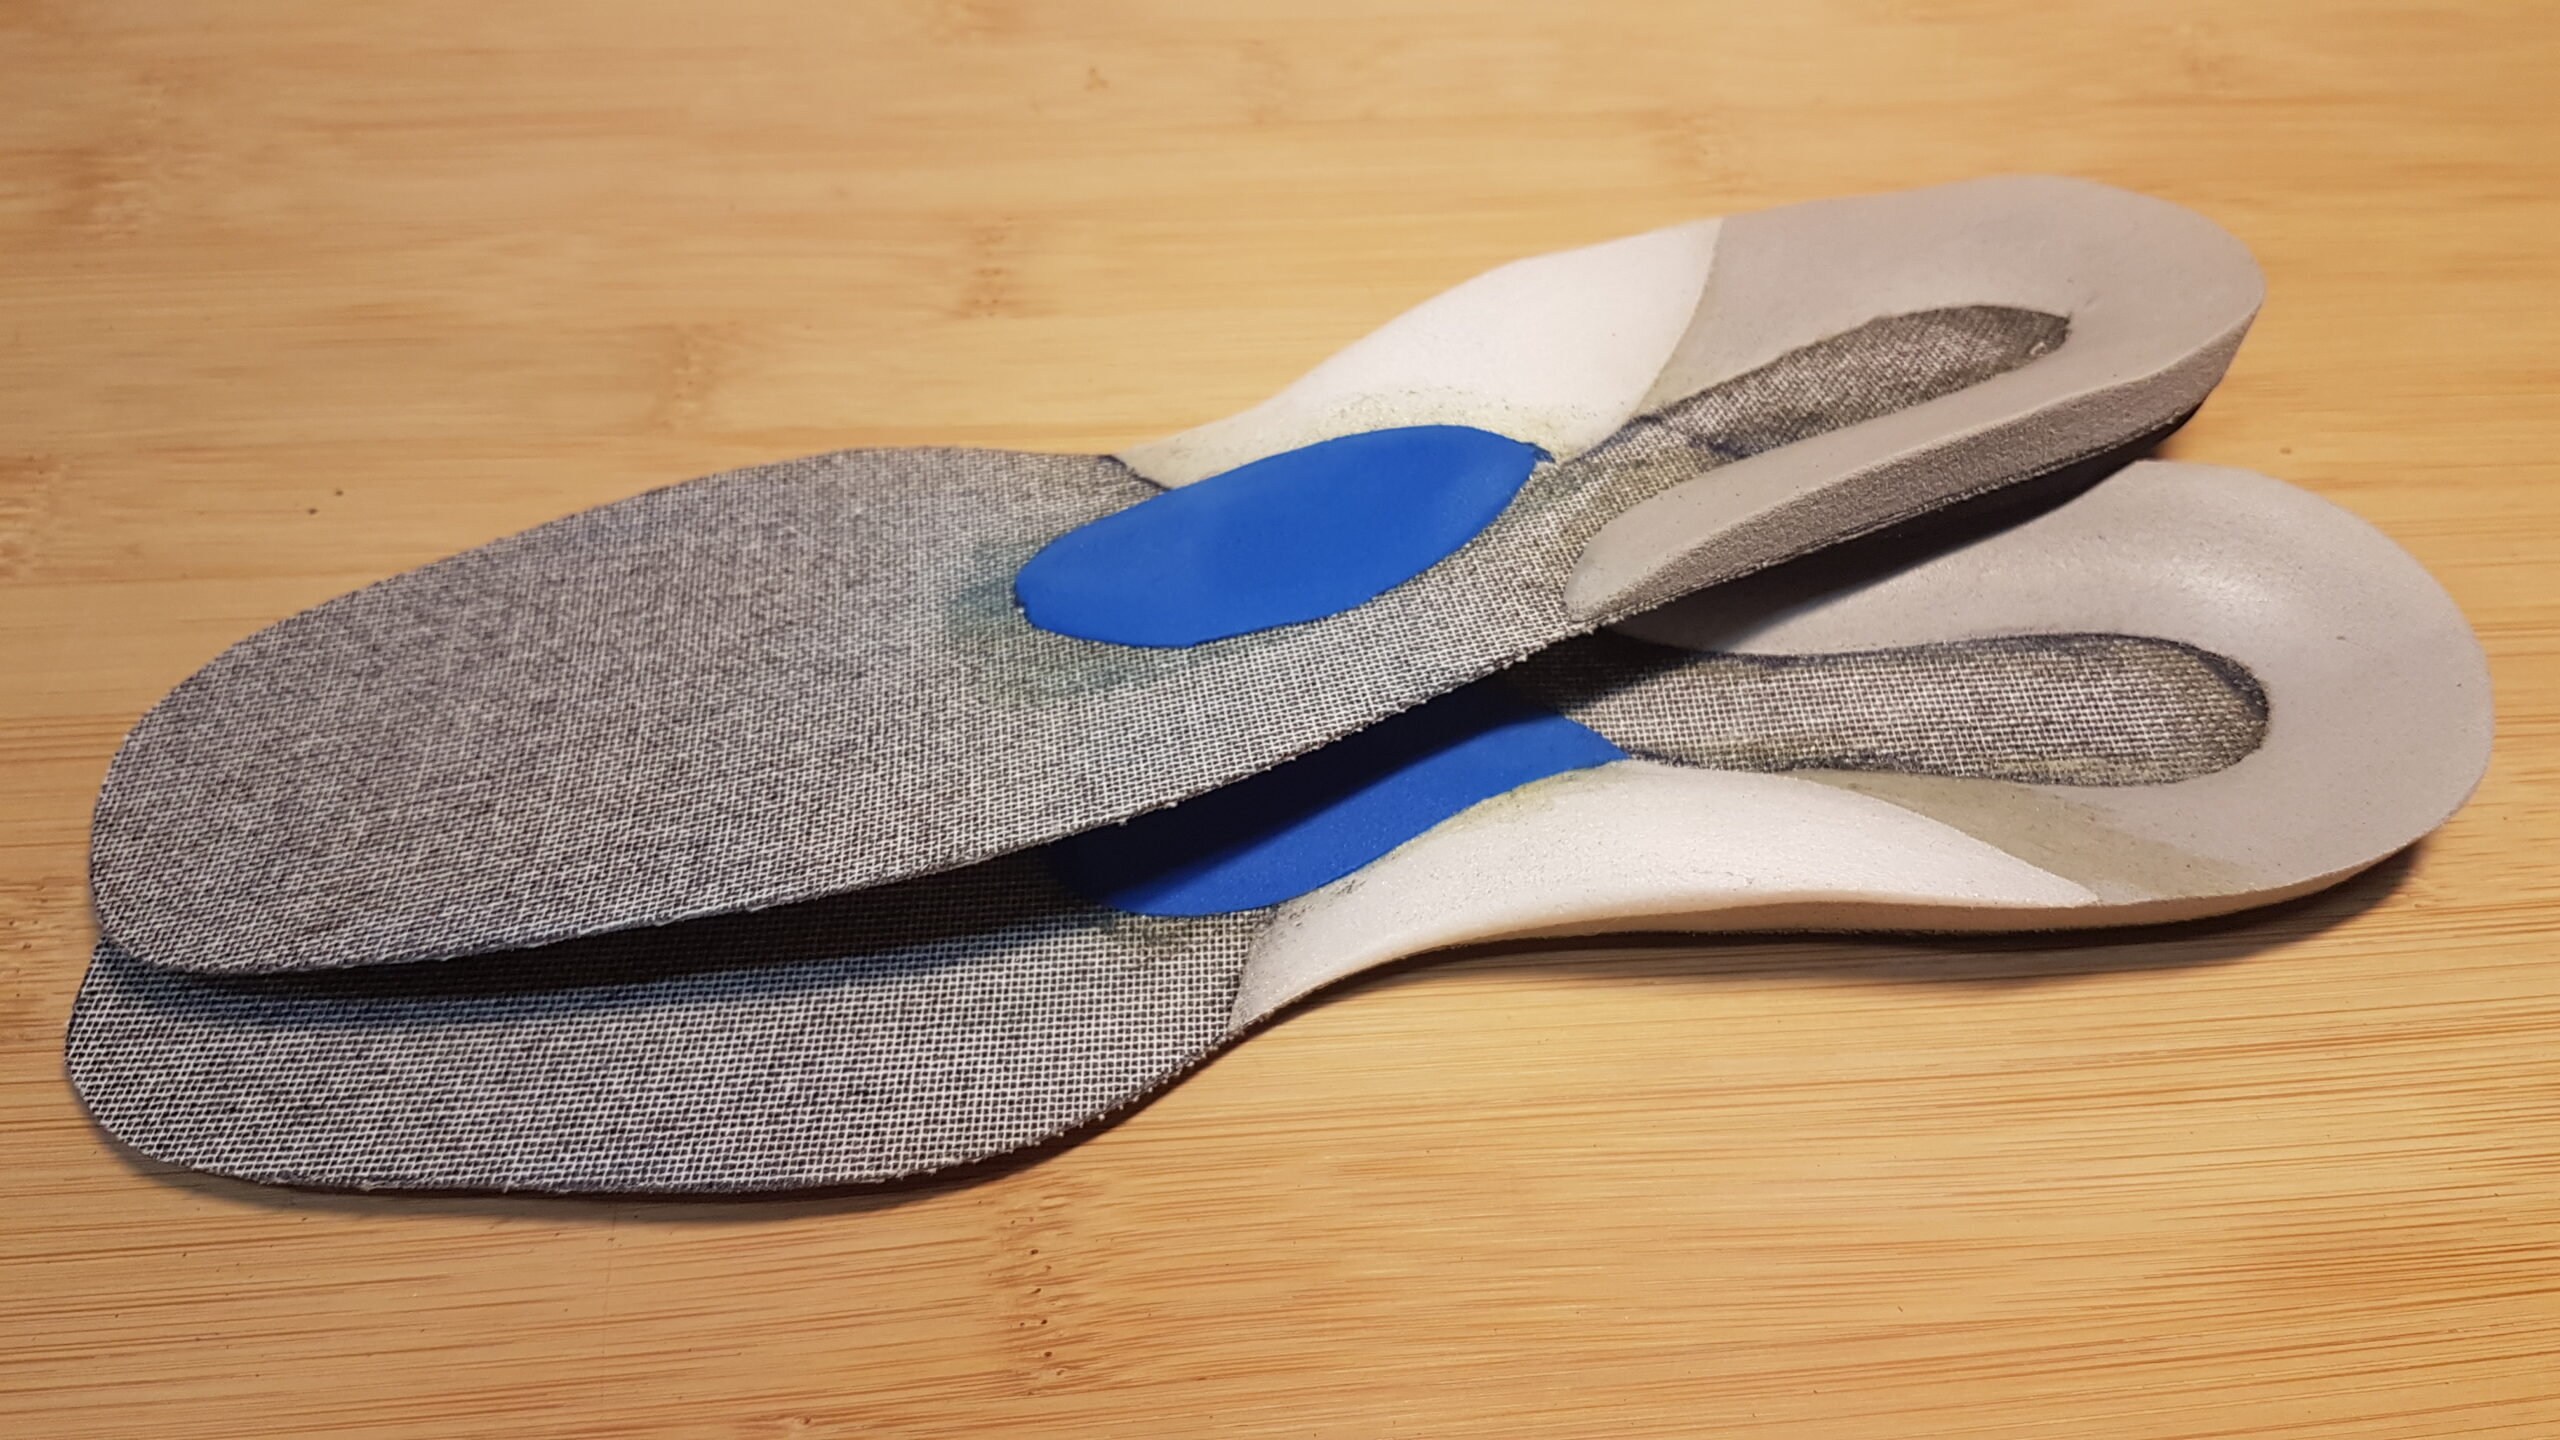

Avant d’envisager une chirurgie, l’orthésiste réalise des orthèses plantaires sur-mesure. Elles seront finement réglées de manière à limiter la déformation.

Une paire d’orthèse plantaire est réalisée en traitement complémentaire aux séances de kinésithérapie prescrites par le médecin. Elles seront portées pendant toute la durée des séances et régulièrement réduites par ponçage pour accompagner la rééducation.

L’orthésiste réalise des semelles orthopédiques sur mesure permettant de décharger le fascia, corriger les défauts d’appui et réduire la tension à l’origine de l’inflammation. La semelle accompagne également la récupération en parallèle des séances de kinésithérapie.

Une semelle orthopédique sur mesure permet de décomprimer l’espace inter-métatarsien, de soulager la pression sur le nerf et d’améliorer significativement le confort à la marche.

Des semelles orthopédiques sur mesure permettent de réduire les contraintes mécaniques sur le genou, corriger les défauts d’appui et accompagner l’adolescent tout au long de sa période de croissance.

Des semelles orthopédiques sur mesure permettent d’amortir les contraintes sur le talon, de surélever le calcanéum et de soulager la tension tendineuse pendant toute la phase de croissance.